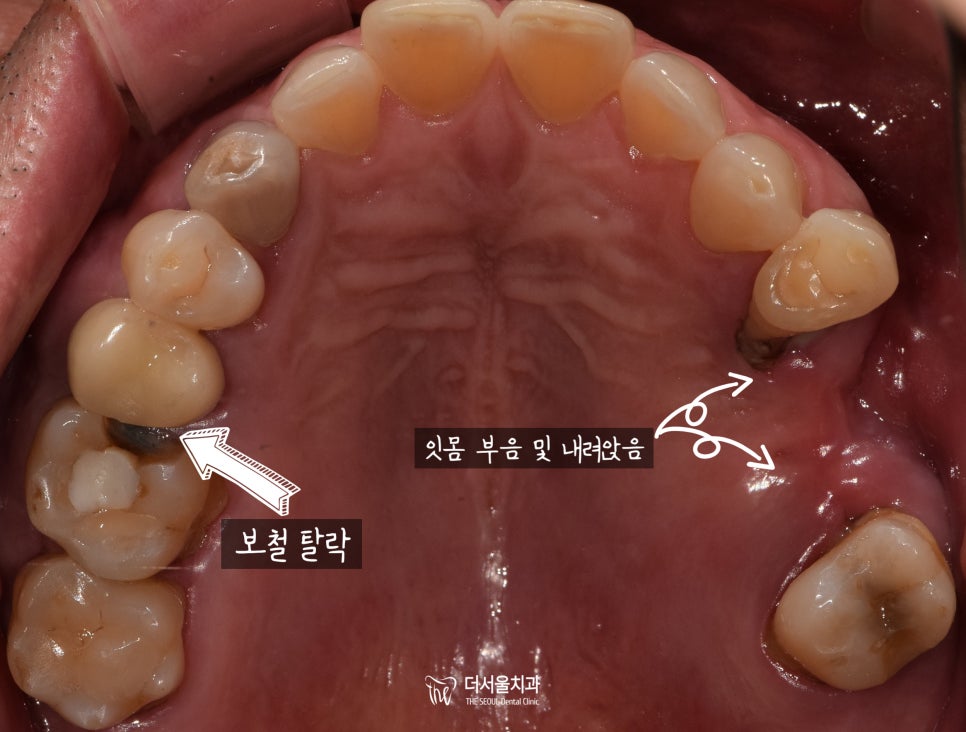

구강 내 상황을 그리 좋지 않았습니다.

먼저 윗니를 살펴보면,

어금니 쪽 떼워놓은 부분이

떨어져있을 뿐만이 아닌

잇몸도 벌겋게 부어있고,

속에 있는 치근이 보여질 정도로

드러난 것을 확인할 수 있습니다.

아랫니 또한 그리 좋지만은 않았습니다.